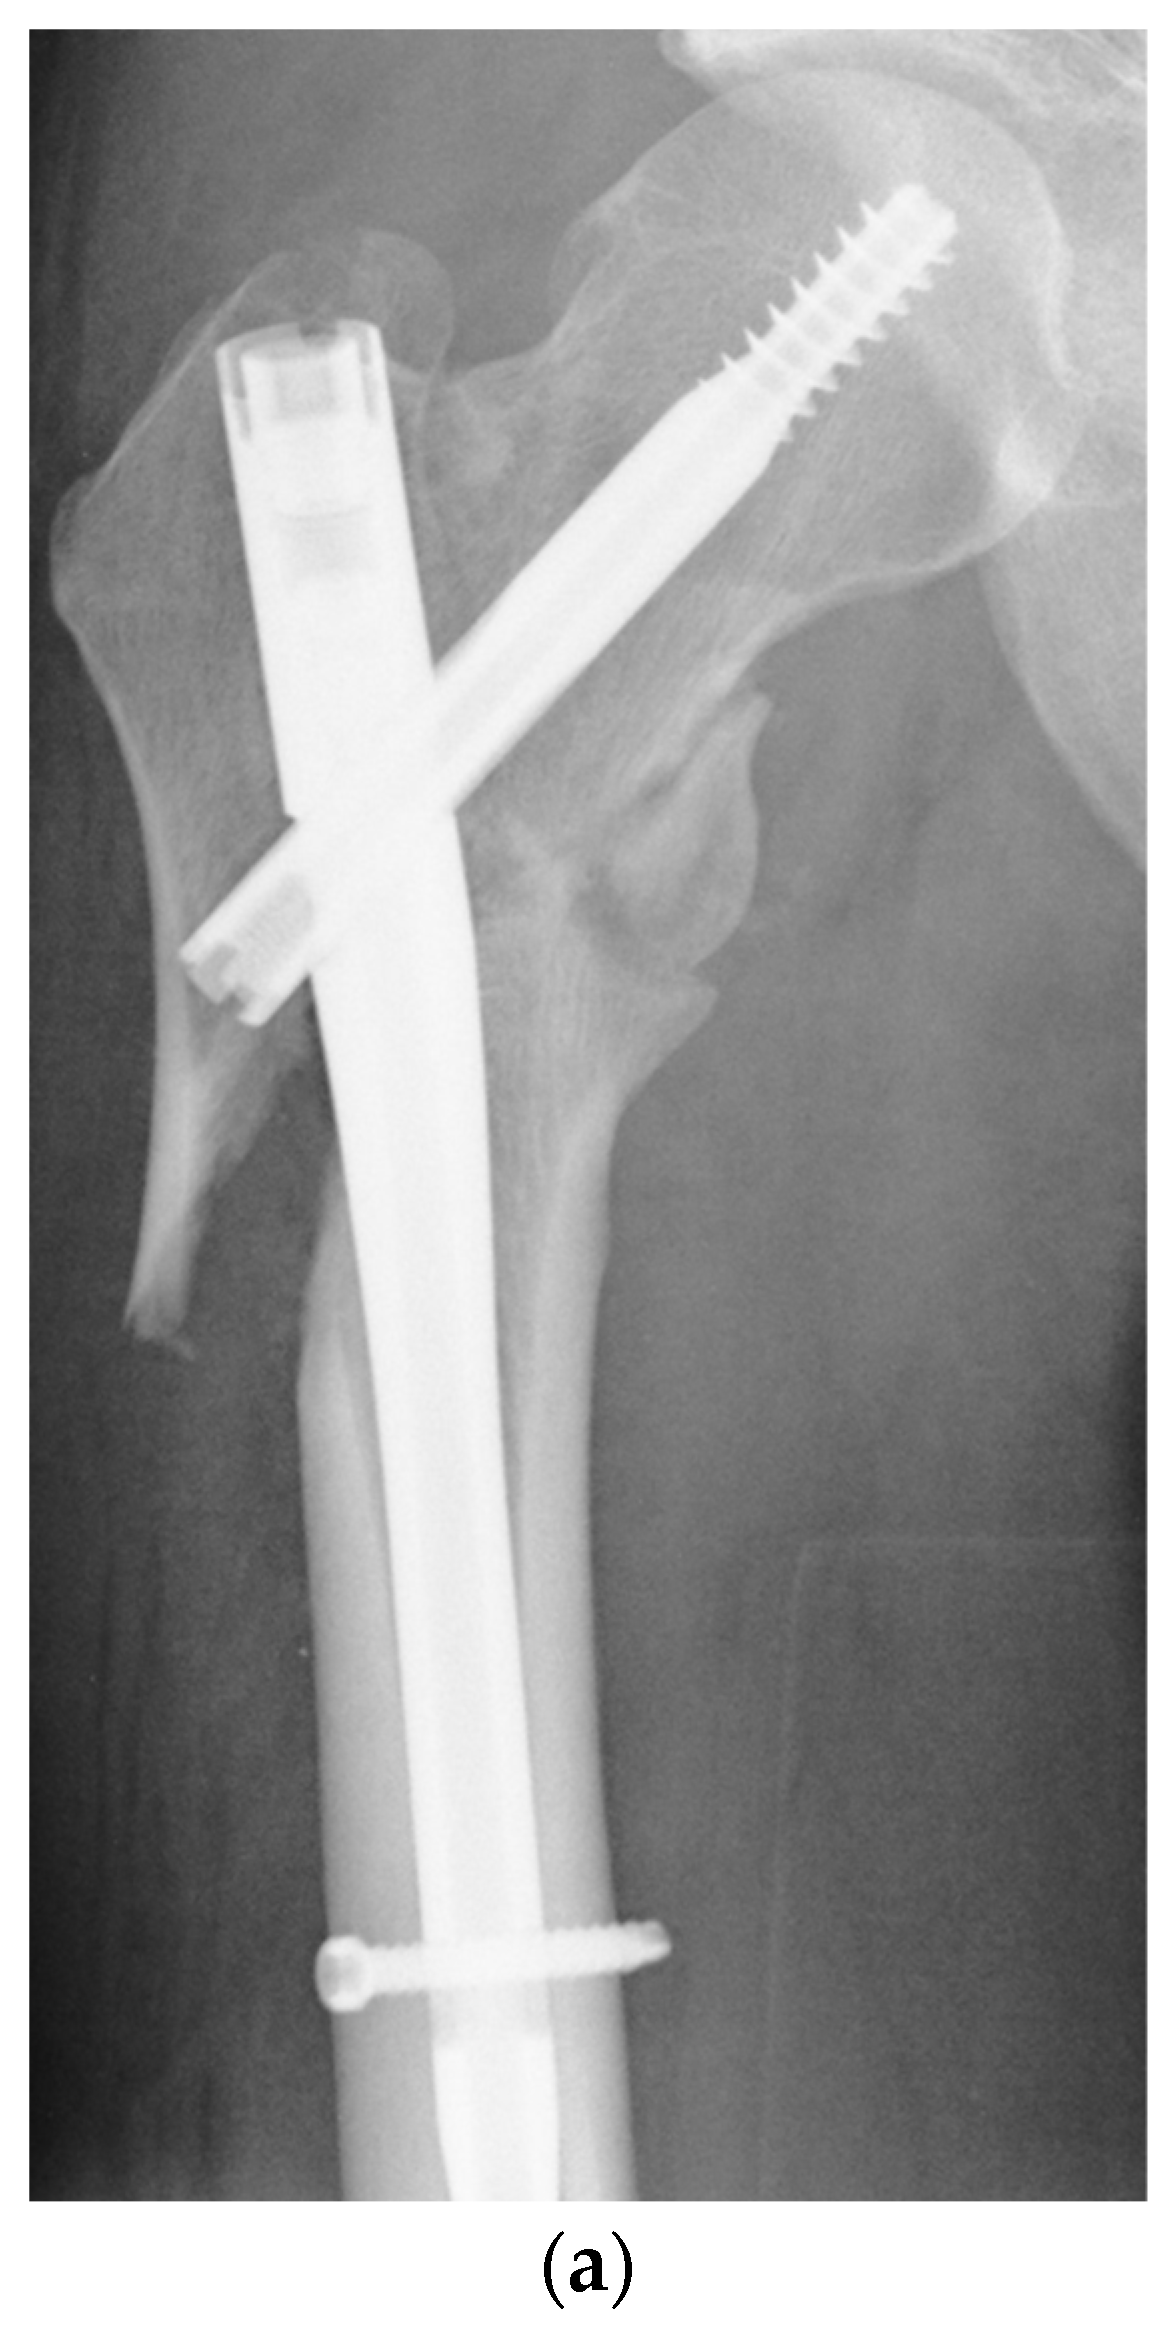

A retrospective analysis of the in-house databases of two European level I trauma centers was carried out for consecutive patients from January 2010 to March 2020. A total of 68 consecutive patients (21 women and 47 men) with the diagnosis of aseptic nonunion following AO/OTA 31 A1, 31 A2, 31 A3, very proximal 32 A13, 32 B13 and 32 C13 fractures were included (Figure 1; p < 0.0001). Patients aged 18 years and older who had undergone surgical revision for trochanteric and subtrochanteric nonunion with revision cephalomedullary nailing (Gamma3®, Stryker Corp., Kalamazoo, MI, USA; Trigen™ Intertan™, Smith & Nephew Inc.; Memphis, TN, USA; Figure 2a–c) and 95-degree angled blade plating (DePuy Synthes GmbH, Oberdorf, Switzerland; Figure 3a–c) were included. Pathologic fractures, fractures treated by total hip arthroplasty (THA) and periprosthetic fractures or extramedullary fixation devices were excluded from the study a priori, as were patients younger than 18 years and patients unable to give consent. The inclusion and exclusion criteria were strictly controlled and respected.

Figure 2. (a) Aseptic nonunion 9 months following cephalomedullary nail fixation in a multi-fragmentary subtrochanteric fracture in a 58-year-old male patient. (b) Osseous healing three months after revision surgery using a 360 mm × 13 mm Intertan™ cephalomedullary nail. (c) Situation after metal removal 36 months following surgical revision.